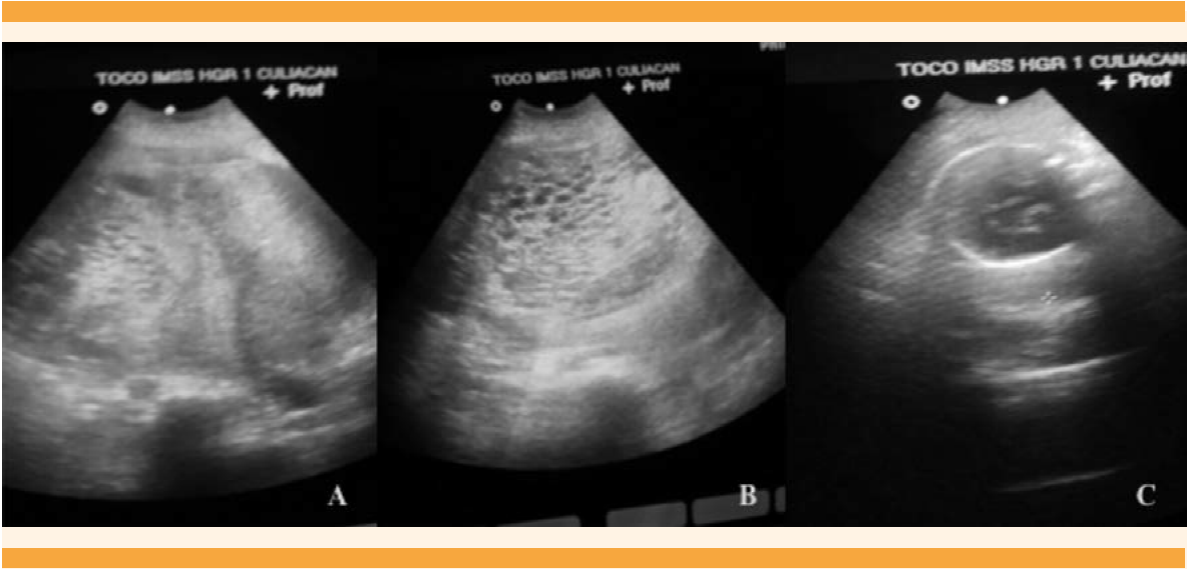

Caso 1. Paciente de 34 años de edad. Dos gestaciones, 1 hijo vivo (nacimiento por cesárea, neonato a término, eutrófico). Embarazo actual de 33 semanas de gestación (SDG) por fecha de última menstruación (FUM). Se hospitaliza por embarazo con mola completa, coexistiendo con feto vivo, sin trabajo de parto. A su ingreso en buen estado general, asintomática. Signos vitales: TA 150/100 mm Hg, FC 83 lpm, FR 19 x, T 360C. La evaluación obstétrica reveló altura del fondo uterino (AFU) mayor al que correspondía para su edad gestacional, feto único vivo intrauterino, frecuencia cardíaca fetal (FCF) con Doppler de 136 lpm. Actividad uterina no palpable. Al tacto vaginal cérvix posterior, blando, cerrado, sin hemorragia uterina, ni salida de líquido amniótico transvaginal. USG abdominopélvico: embarazo molar, con feto único vivo de 31 semanas de gestación ocupando una de las cavidades amnióticas. Una placenta normal, localizada en el fondo y cara anterior del útero; además, se observó una segunda placenta con múltiples cavidades quísticas en “panal de abejas”, e índice de líquido amniótico de 8. Figuras 1 y 2

Figura 1 Ultrasonido abdominopélvico del tercer trimestre del embarazo (Caso 1). A: Corte sagital del útero que muestra el embarazo gemelar, con dos placentas y dos bolsas amnióticas. B: Primera placenta con masa ecogénica que contiene numerosos espacios quísticos (imagen en “panal de abeja”) que corresponden a las vellosidades coriónicas marcadamente hidrópicas, con ausencia de feto. Segunda placenta de aspecto normal. C: Feto vivo de 31 semanas que ocupa la segunda bolsa amniótica, con placenta normal.

La coexistencia de embarazo gemelar con mola completa ocurre en 1 de cada 22,000 a 100,000 embarazos y es aún más raro con feto superviviente.10 En este artículo se reporta el caso de una paciente con embarazo gemelar, con mola clásica o completa, feto vivo coexistente (Figura 1) hasta su nacimiento a las 33 semanas de gestación. El aspecto macroscópico mostró claramente dos placentas: una de aspecto normal y la otra con vellosidades edematosas, con la imagen clásica de mola hidatiforme con “vellosidades en racimo de uvas”. Figura 2